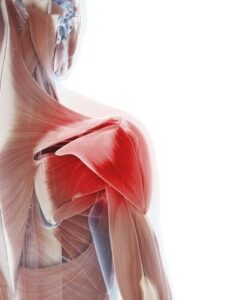

Many people experience shoulder pain when lifting their arm overhead, reaching for objects, or performing everyday activities such as getting dressed or exercising. This type of discomfort can occur for several reasons and often develops gradually due to muscle strain, joint restriction, or irritation of the surrounding tissues.

If you are noticing pain when raising your arm, it may indicate irritation within the shoulder joint, muscular tension, or limited mobility affecting how the shoulder moves.

Because the shoulder relies on coordinated movement between the shoulder blade, upper back, and surrounding muscles, restrictions in any of these areas can create discomfort when lifting the arm.

Rotator Cuff Irritation

The rotator cuff muscles help stabilize and move the shoulder joint. When these muscles become irritated or overworked, lifting the arm overhead may cause pain, weakness, or a pinching sensation. Rotator cuff irritation can occur from repetitive lifting, sports activity, poor posture, or prolonged strain on the shoulder.

Shoulder impingement occurs when structures within the shoulder joint become compressed during movement. This often causes pain when raising the arm above shoulder height or reaching behind the back. Impingement may develop gradually due to muscular imbalance, restricted mobility, or repetitive overhead activity.